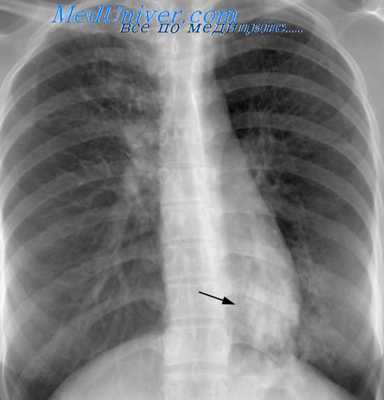

Заболевание может начинаться остро или подостро; маскироваться под грипп, острую пневмонию, плеврит либо протекать бессимптомно. Клинические проявления включают интоксикационный синдром, субфебрилитет, кашель, одышку. Изменения в первичном очаге проходят инфильтративную фазу, фазу рассасывания, уплотнения и кальцинации (формирования очага Гона).

Первичный туберкулезный комплекс сочетает в себе признаки специфического воспаления в легком и регионарный бронхоаденит. Может протекать бессимптомно или под маской простудных заболеваний, поэтому выявлению первичного туберкулеза легких способствуют массовые скрининги детей (проба Манту) и взрослых (профилактическая флюорография).

Чаще возникает подостро: больного беспокоит сухой кашель, субфебрилитет, утомляемость, потливость. При острой манифестации клиника напоминает неспецифическую пневмонию (высокая лихорадка, кашель, боль в груди, одышка). В результате лечения происходит рассасывание или обызвествление ПТК (очаг Гона). В неблагоприятных случаях может осложняться казеозной пневмонией, образованием каверн, туберкулезным плевритом, милиарным туберкулезом, диссеминацией микобактерий с поражением почек, костей, мозговых оболочек.